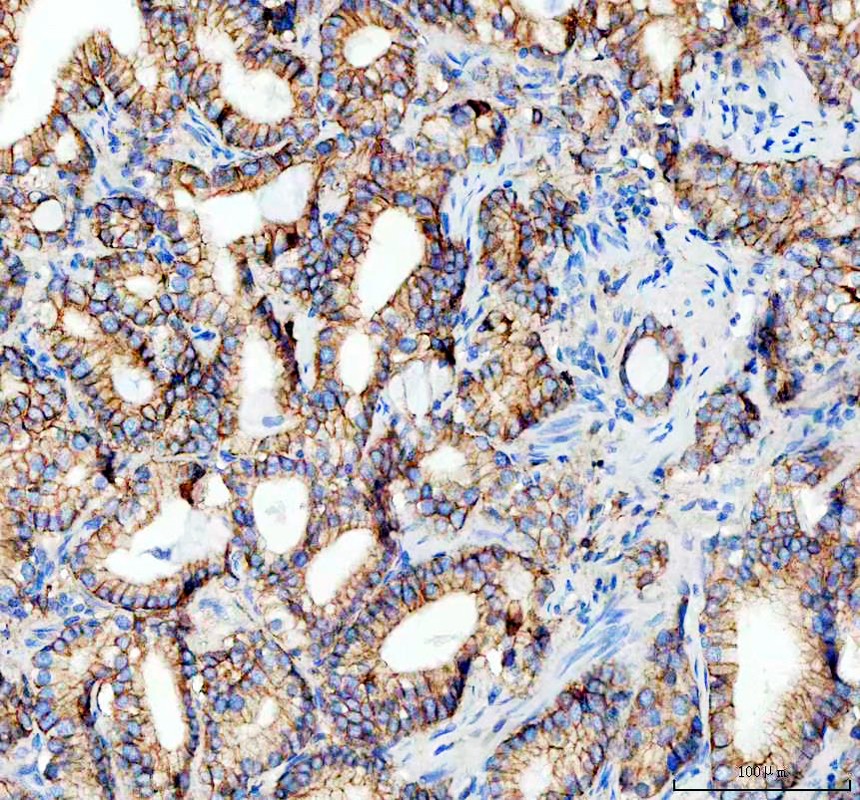

IHC analysis of E-cadherin/CDH1 using anti-E-cadherin/CDH1 antibody (M00063-2).

E-cadherin/CDH1 was detected in a paraffin-embedded section of human colorectal adenocarcinoma tissue. The tissue section was incubated with mouse anti-E-cadherin/CDH1 Antibody (M00063-2) at a dilution of 1:200 and developed using HRP Conjugated mouse IgG Super Vision Assay Kit (Catalog # SV0001) with DAB (Catalog # AR1027) as the chromogen.